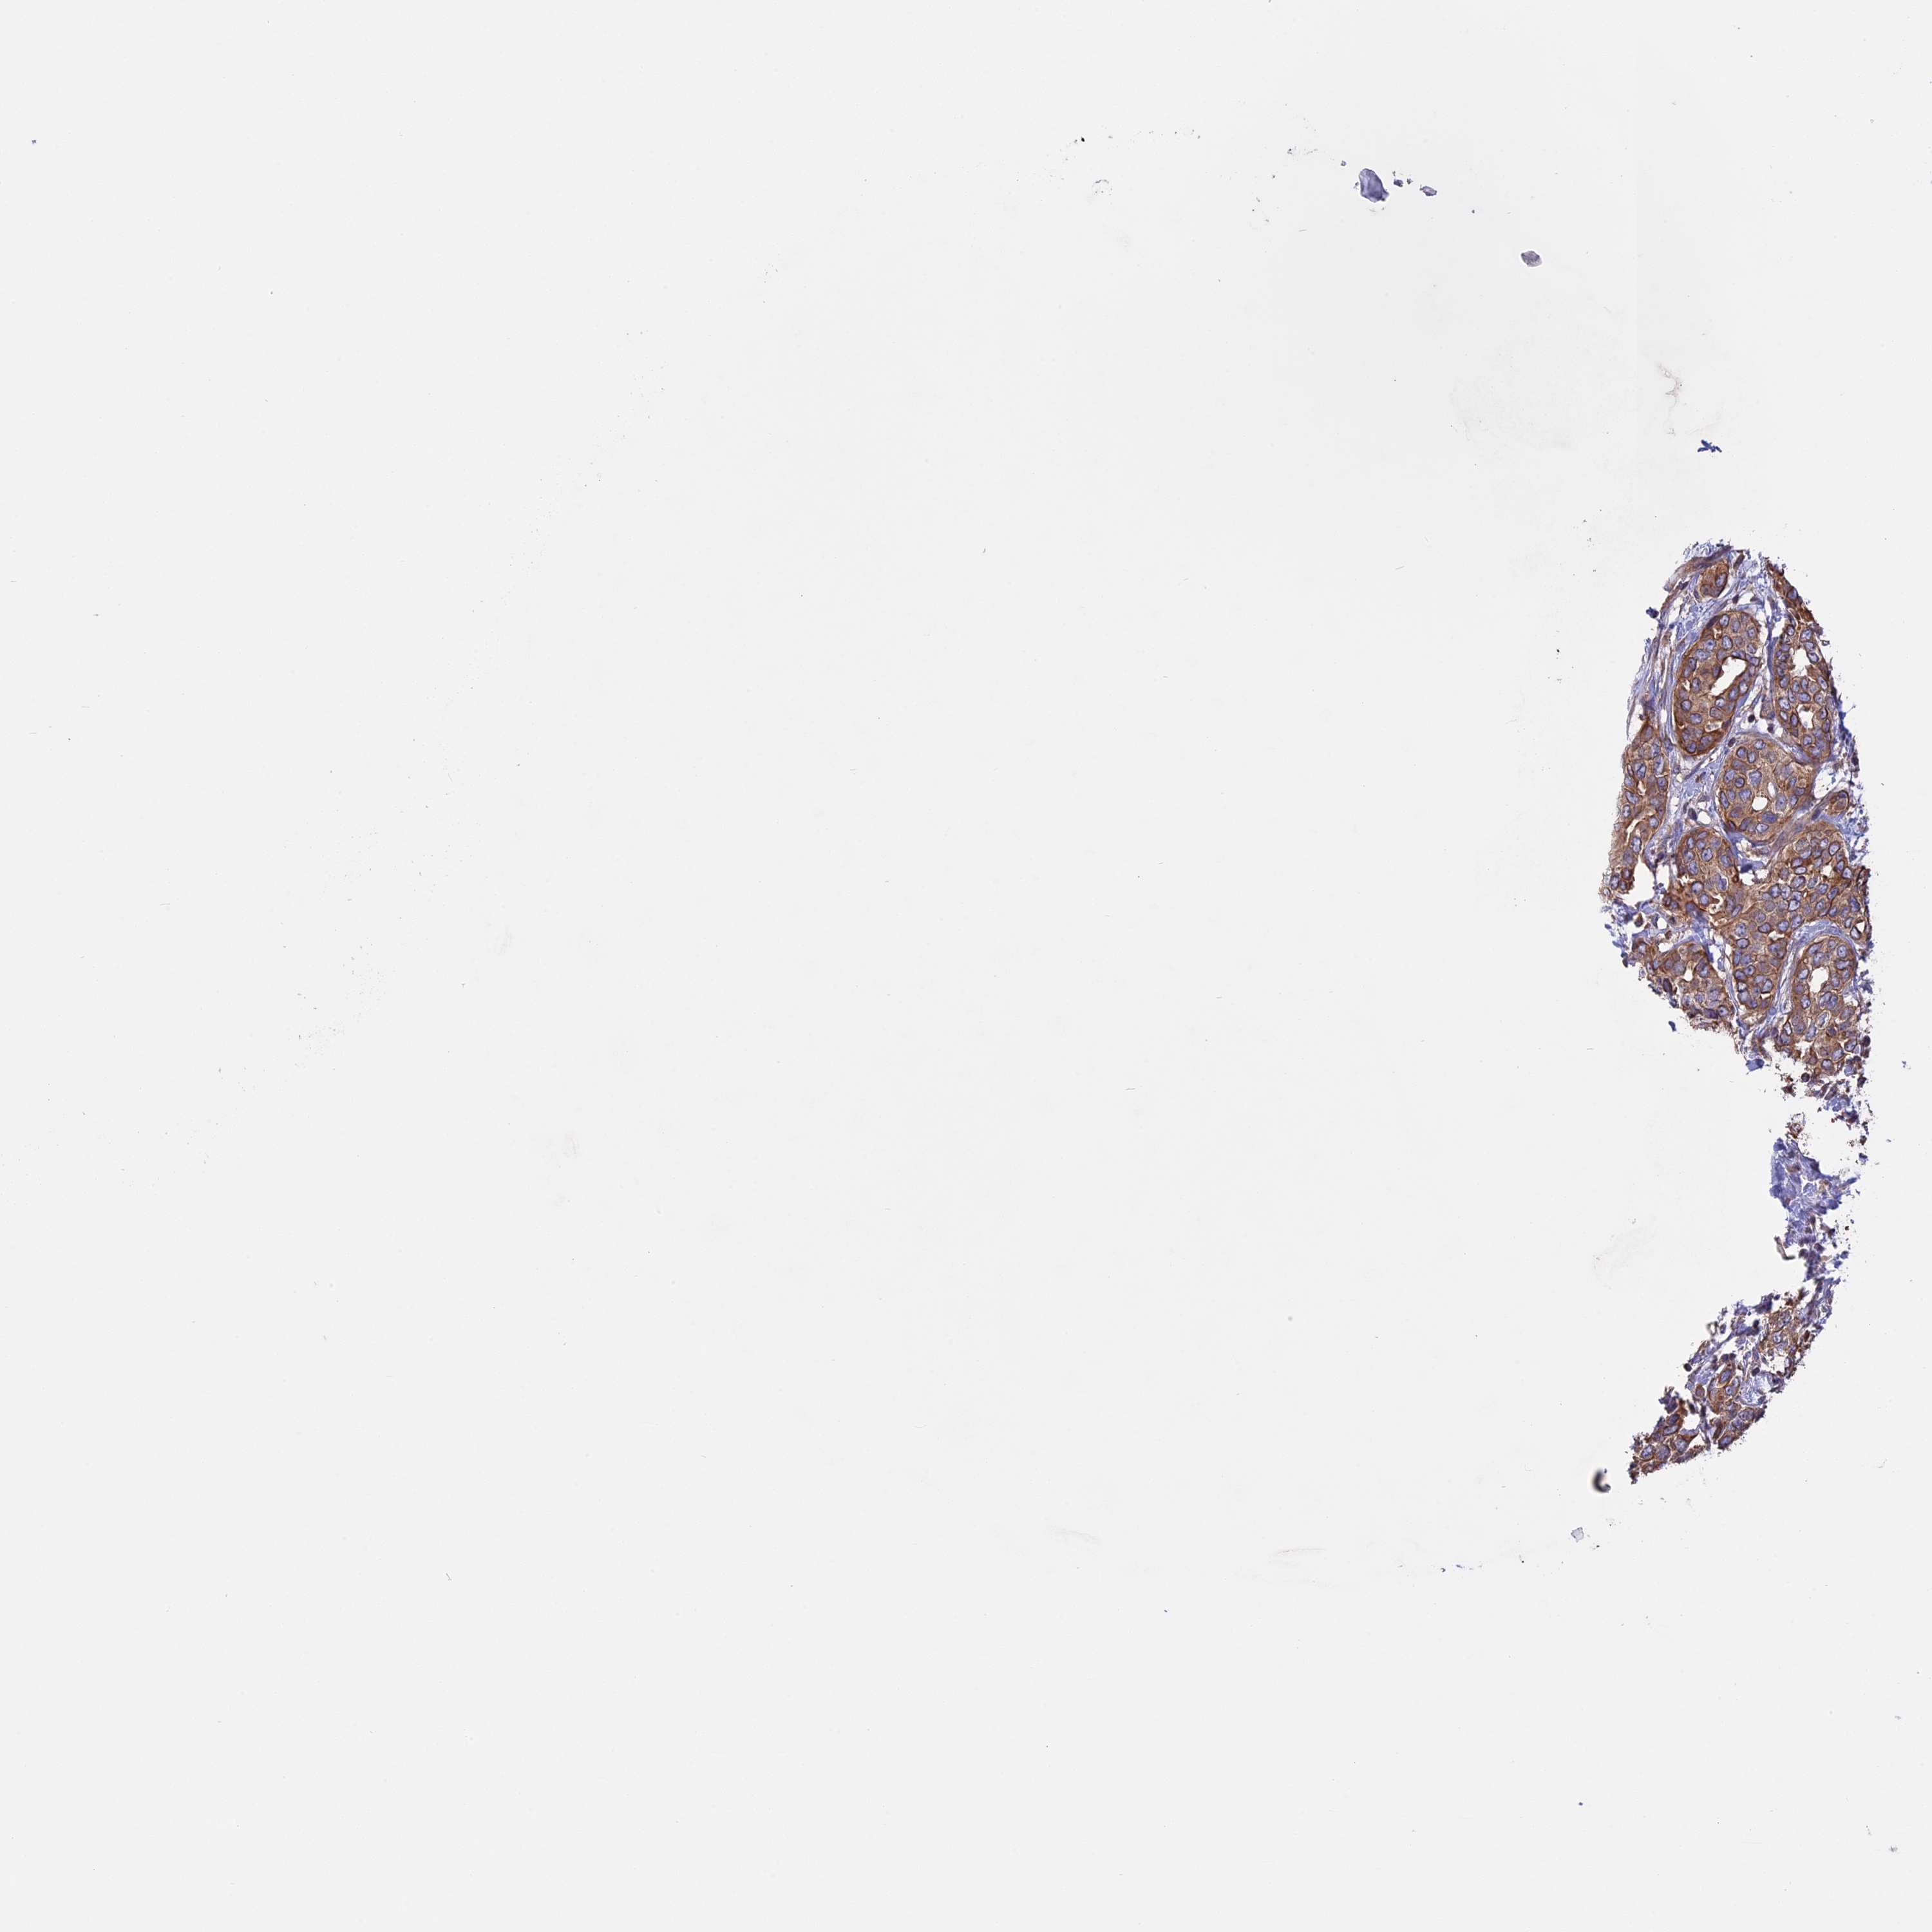

CANCER BREAST CANCER Show tissue menu

BRCA TCGA BRCA VALIDATION PROTEIN EXPRESSION